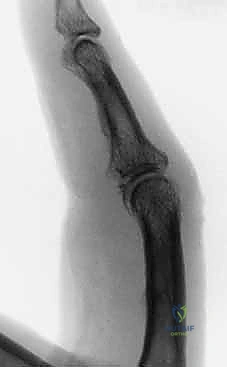

Figures 1A and 1B (TECH FIG 1A,B) show us marking the position for the first wire at the level of the center of rotation of the PIP joint, confirmed with the image intensifier.

-

Determine Entry Point: Aim to insert the wire 1 to 2 mm proximal to the marked center of rotation.

> SURGICAL WARNING: Aiming slightly proximal is crucial. The joint capsule reflects proximally from the articular margin. By staying 1-2mm proximal, we ensure the wire remains extracapsular. A distal wire, penetrating the joint capsule, significantly increases the risk of joint infection if pin track sepsis develops, leading to catastrophic outcomes. Conversely, placing this wire too far proximally in the diaphysis of the proximal phalanx will restrict full joint movement, defeating the purpose of a dynamic fixator. This balance is key. -

Initial Wire Insertion: Take your 1.1-mm K-wire and, under direct visualization and fluoroscopic guidance, initiate insertion through the skin and subcutaneous tissue. Aim for the center of the proximal phalanx in both PA and lateral planes. Ensure it is perpendicular to the long axis of the finger and parallel to the intended plane of rotation of the joint.

> PEARL: As you insert, you should feel the resistance of the cortical bone. Advance slowly, using a drill with a controlled, oscillating motion to prevent thermal necrosis of the bone. -

Fluoroscopic Confirmation (Partial Insertion): Insert the wire partially through the proximal phalanx, ensuring it crosses the head of the proximal phalanx. Immediately check its position with both true posteroanterior (PA) and lateral projections on the image intensifier.

Figure 1C (TECH FIG 1C) confirms the wire inserted across the head of the proximal phalanx, verified on the image intensifier, before further advancement.

- Finalize Proximal Wire Placement: Once confirmed, advance the wire fully through the bone, ensuring equal lengths are present on either side of the finger. This symmetry, while less critical for the proximal wire, will serve as a useful guide for balancing the distal wire later.